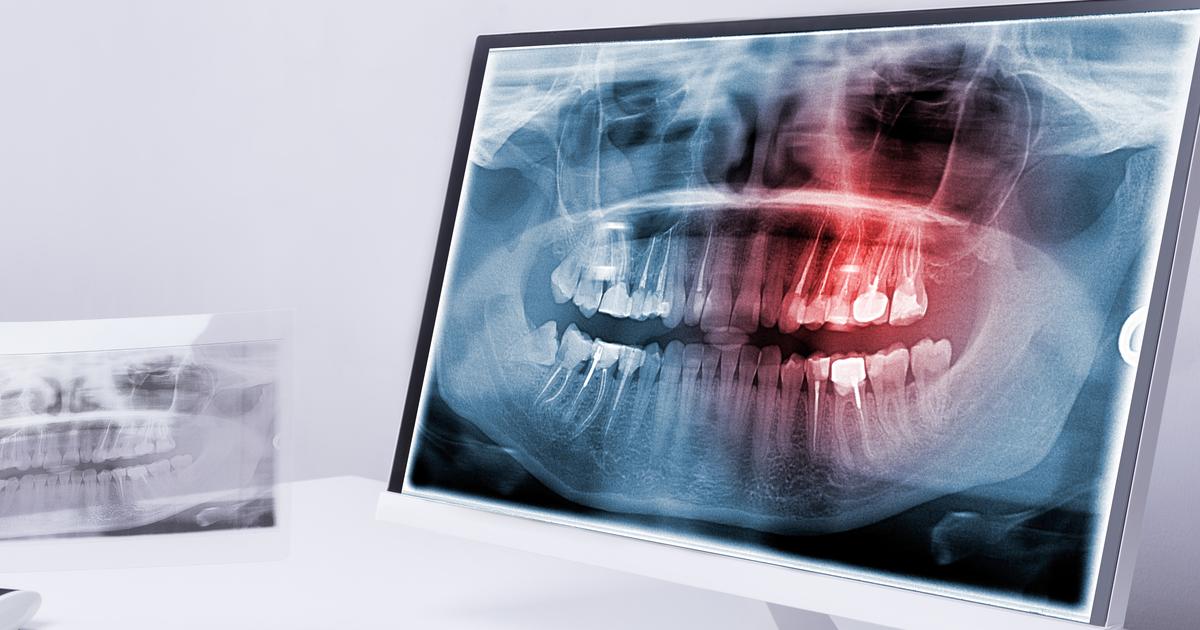

Infections at the dental implant site often happen when the immune system triggers the inflammation response to attack the surrounding bone and gum tissue. It can also occur when peri-implantitis causes the gum and bone surrounding the implant to become inflamed and may cause the loss of bone density in the surrounding bone. This occurs when bacteria is introduced to the surgical area. Bacteria can be introduced throughout the different stages of operation if the dentist does not observe the proper protocol for dental hygiene. It may happen if the equipment isnât sterile or if the implant is contaminated. It may also occur if the patient has an untreated infection. Peri-implantitis often occurs years after the surgery and is more likely to happen in individuals who smoke or have diabetes, poor immune systems, thin gums, or poor dental hygiene. If patients notice their gums look red or purple, if there is pus coming out from the implant, or abnormal bleeding at the gum line, they may have peri-implantitis. The dentist will need to reopen the gums to clean the area to remove the bacteria. A bone graft might also be necessary if there is bone loss, and severe cases might need to remove the dental implant.

Bone Loss

The placement of dental implants may put an individual at an increased risk of having bone loss in the years following the installation. Peri-implantitis is an infection that affects the soft tissue around the bone-integrated implant. The pathophysiology of this particular type of infection is known to be associated with a disruption in the equilibrium between an individual's defense system in the body and the microflora in their oral cavity. Plaque with microbial properties can form on the surface of an individual's dental implant the same way it can build up on the natural tooth surface. The soft tissues around the implant abutment become infected and inflamed due to the tissue's response to the bacterial presence. This infection can spread into the actual tissues of the bone itself around the implant fusion. Peri-implantitis often results in the breakdown of alveolar bone that surrounds the implant. It is estimated between ten and twenty percent of all patients who have a dental implant installed experience alveolar bone loss after the implant has been functional for about a decade. Bone loss following implant installation is technically defined by a bone loss of 1.5 millimeters as referenced on a radiograph within the first year or greater than 0.2 millimeters of bone loss for each subsequent year. Early treatment of this infection can prevent dental implant-associated bone loss.